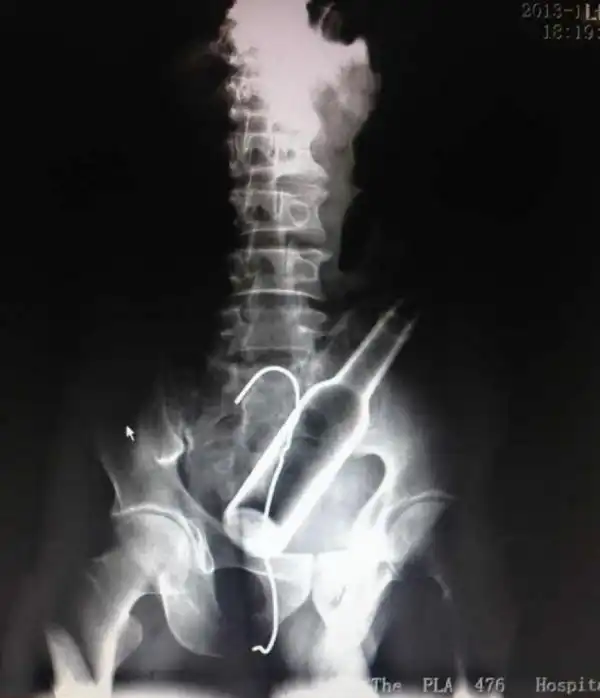

Врачебные находки в интимных местах

Или как впихнуть невпихуемое :lol: